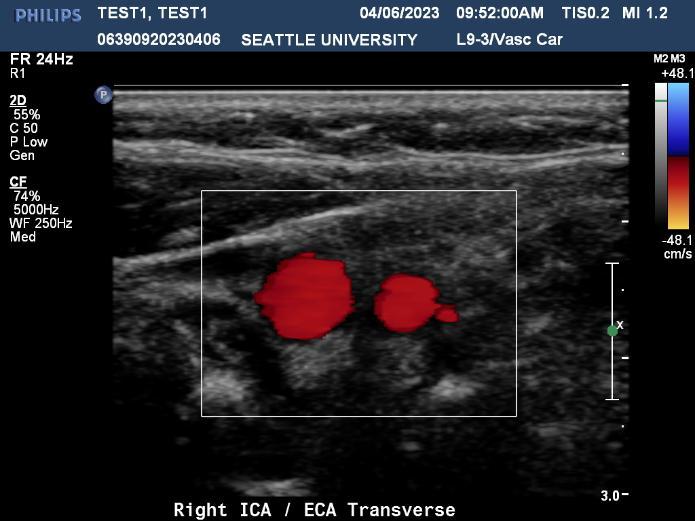

Ultrasound is a non-invasive diagnostic tool that uses high-frequency sound waves to propagate images of organs and tissues within the body. The Diagnostic Ultrasound program at Seattle University offers three distinctive track specializations in General (abdomen extended, OB/GYN) Vascular and Cardiac sonography.